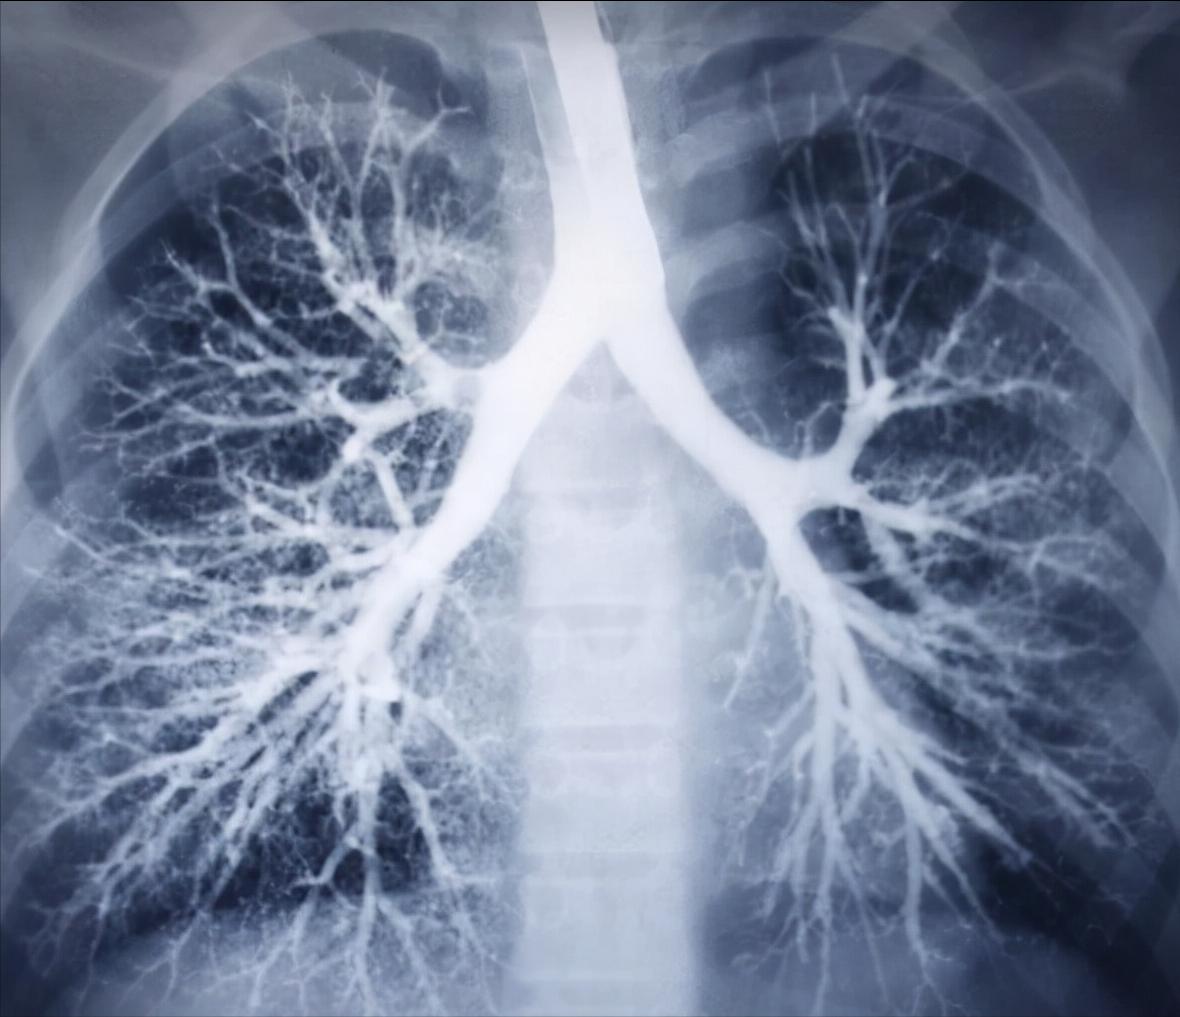

白色的树杈样的就是肺纹理呦

肺纹理,其实就相当于一棵树的树枝,在影像学上因难以穿透,所以在片子上一般呈现的是白色条纹状,跟树杈一样;那有些人也好奇树叶呢,相当于啥呢?树叶就是肺泡;枝呢,其实就是肺里面的血管、气管、甚至淋巴管,很明显这些都是管状的,呈条索样;